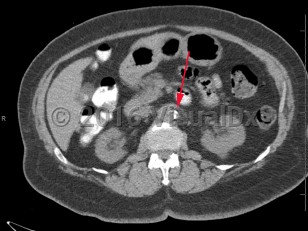

Renal artery stenosis is narrowing or blockage of renal artery / arteries. Causes include atherosclerosis, fibromuscular dysplasia, thrombosis, embolism, or external pressure. Reduced renal perfusion can lead to renovascular hypertension as well as acute or chronic kidney injury.